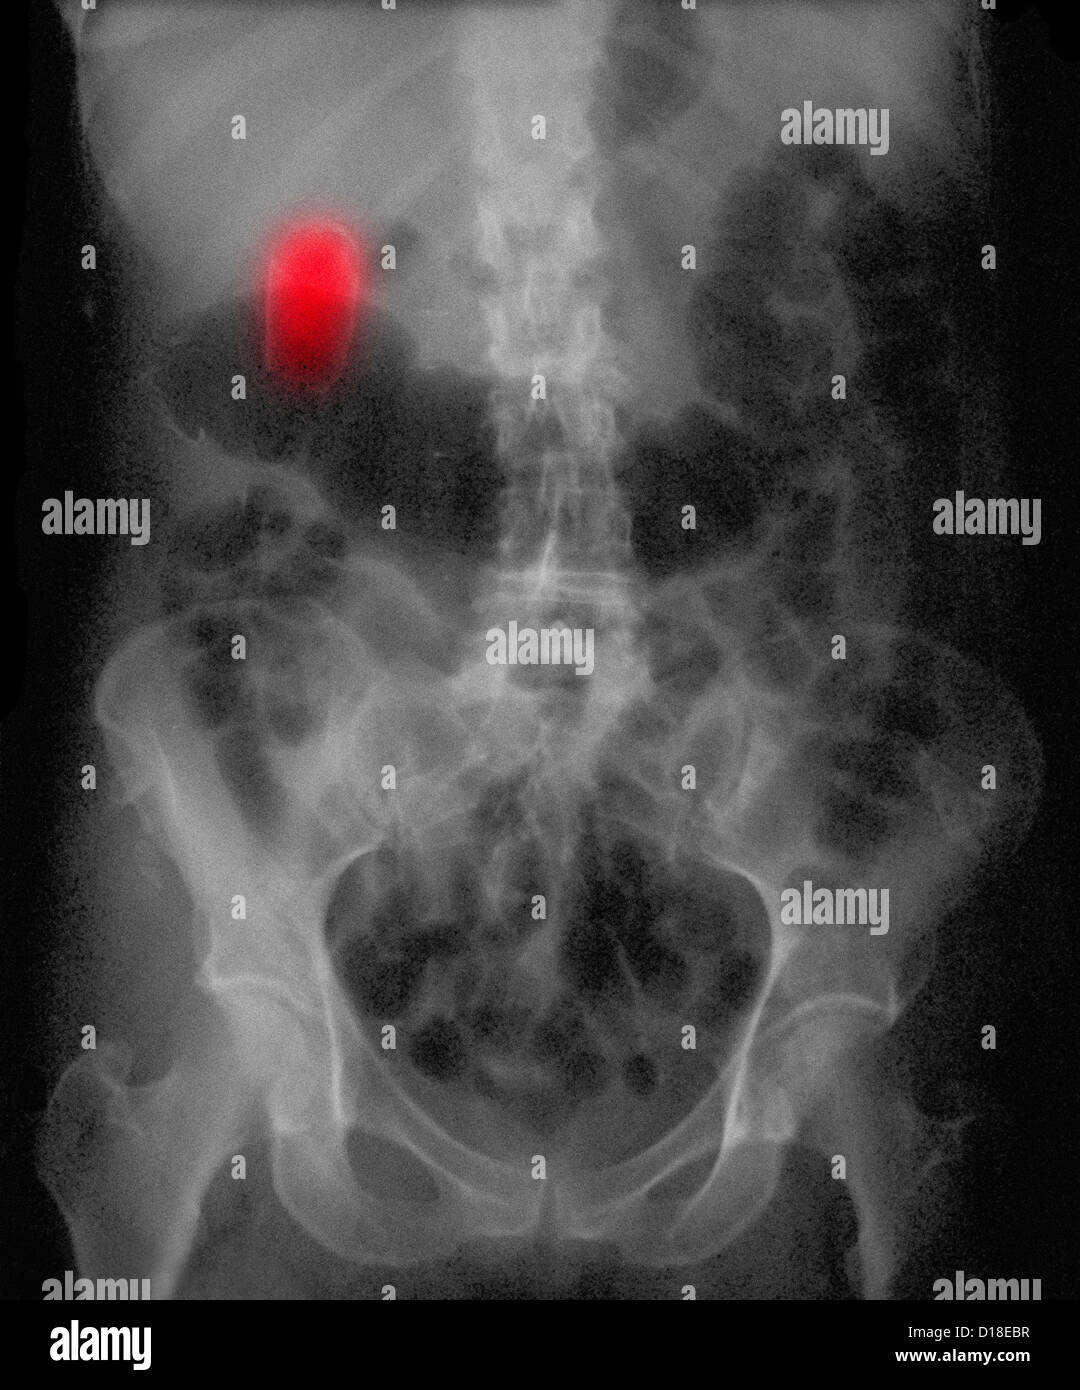

From www.alamy.com

Xray showing a socalled porcelain gallbladder Stock Photo Alamy What Is A Porcelain Gallbladder Learn about porcelain gallbladder, a condition characterized by the calcification of the gallbladder wall. The wall becomes brittle, hard, and often takes on a bluish hue. Porcelain gb is a complete or partial calcification of the entire gb wall thickness or its mucosal layer that is visualized on plain. Porcelain gallbladder is a rare condition characterized by complete or scattered. What Is A Porcelain Gallbladder.